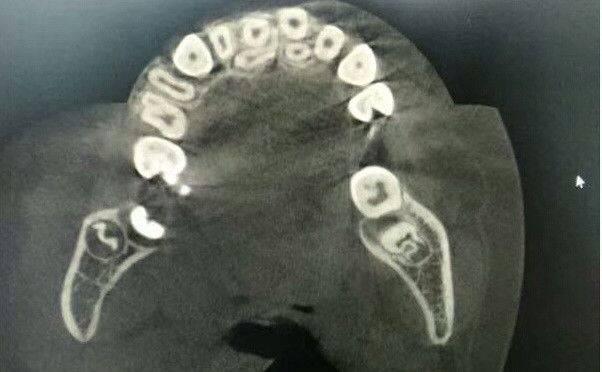

一般来说,乳牙不齐的宝宝无需做特殊处理。但3-4岁宝宝极易出现乳牙反颌(地包天)畸形。

出现这种情况时应及时矫正,妨碍颌骨的发育。如果错过黄金治疗期,甚至会动用到截骨手术!